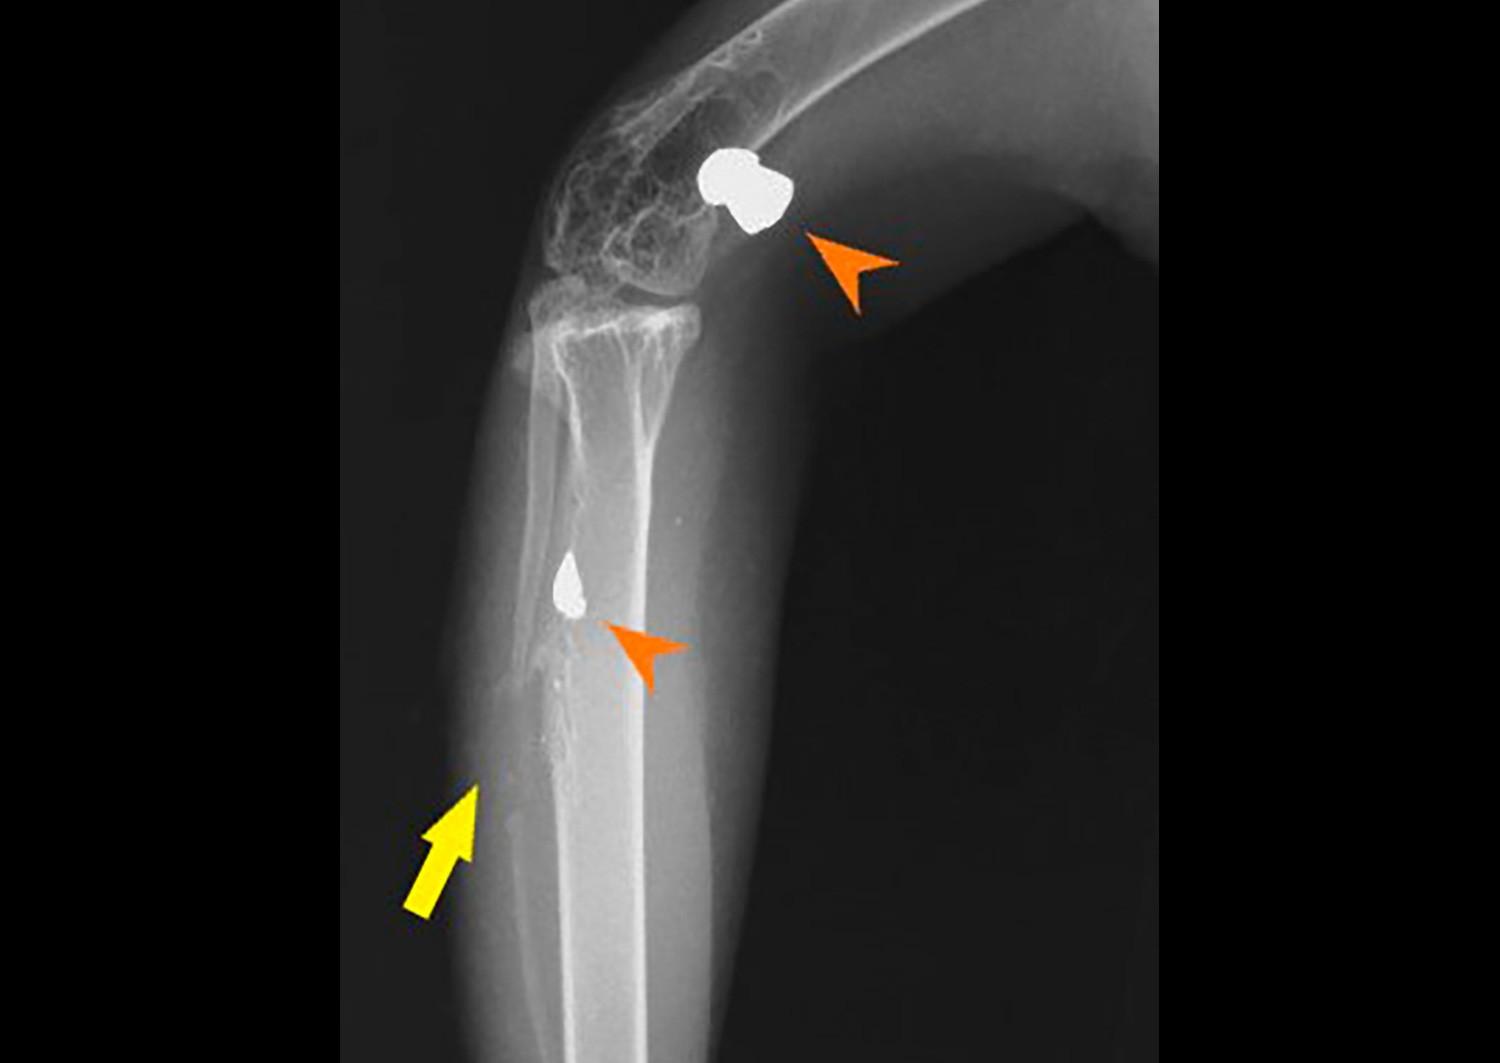

該隻鳳頭鷹最近因翅膀受傷,被送到園方的野生動物拯救中心。在進行X光檢查時,團隊發現牠的腿部隱藏著另一處傷勢,牠的右腿曾被氣槍鋼彈擊中。衝擊力不但打斷了右腓骨,還使鋼彈碎裂,一塊較大的碎片移動到去膝關節,另一塊較小的碎片則嵌入脛跗骨中。園方分析這個傷勢已經有一段時間,令人意外是該隻鳳頭鷹仍能正常使用牠的腳和爪。

園方通過一個小的皮膚切口,輕鬆取出較大的鋼彈碎片;至於較小且深的碎片,則因移除的風險大於好處,而被保留下來。經過幾天的傷口處理後,資深獸醫為鳳頭鷹受傷的翅膀進行了修復手術。鳳頭鷹目前康復進度良好,並正在進行康復訓練,為重返大自然做好準備。